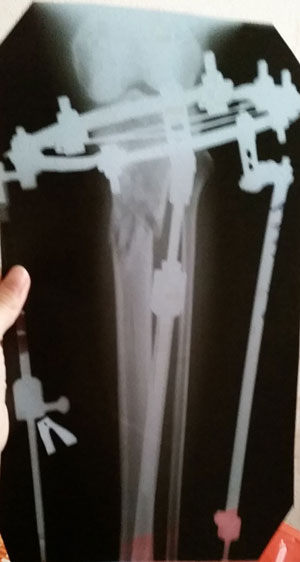

рентген в 90 дней с момента операции.

Ураа аЗдравствуйте, Ласка! По рентгену всё идёт хорошо, регенерат хороший, всё по плану. Через месяц будем готовиться к снятию аппаратов! (предварительно сделав рентген и выслав нам).